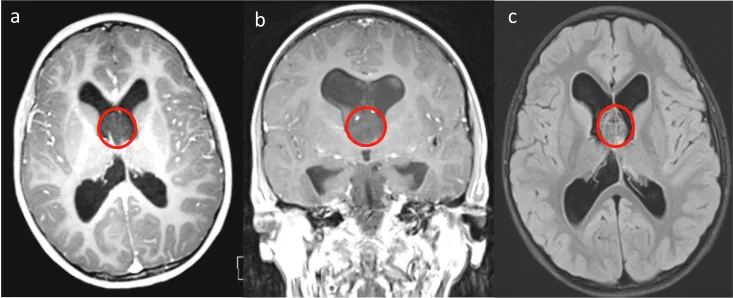

7岁男孩,3周头痛病史,磁共振成像显示在透明隔中伴有脑积水的实质肿块

术前MR成像,T1加权序列(a–b)和轴向深色流体序列(c)显示肿瘤位于透明隔隔膜